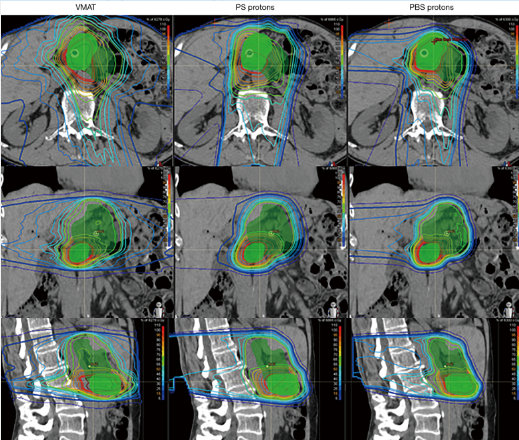

根治性放疗:日本的一项研究针对质子治疗联合化疗治疗局部晚期胰腺癌的效果进行了评估。研究结果显示,质子治疗联合化疗的1年局部控制率和总生存率分别为100%和80%[7]。

▲传统放疗、被动散射质子治疗和 (PS) 和笔形束扫描质子治疗 (PBS) 胰腺癌的剂量分布图,图源:参考来源[7]